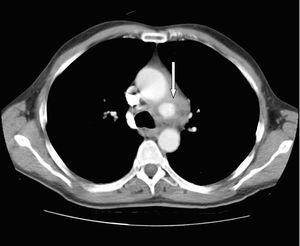

Figura 3. Tomografía computarizada de tórax: imagen de aneurisma en cayado aórtico (flecha).